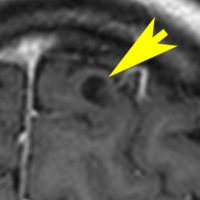

NF-1とNF-2の水頭症

- 多くの場合は過形成性グリオーシスで,中脳水道という髄液の流れ道がつまって水頭症(中脳水道閉塞)になります。これは急に症状を出すことがなくて慢性の頭痛とかを生じる停止性水頭症になりやすいです。治療は,内視鏡を使って髄液の通り道をあける第3脳室開窓術というのをしたら治ります。

- もう一つ,NF-2に生じる現象ですが,脳腫瘍が多発することによって髄液吸収障害が生じて,交通性水頭症になります。この場合に,特に気を付けなければならないのが脳室が大きくならない (slit ventricle) ので,水頭症ではないと思ってしまうことです。眼底検査をすると,うっ血乳頭かあるいは乳頭萎縮の所見があります。急いで,脳室腹腔シャントをしなければなりませんが,定位脳手術でしか脳室端を刺入することができません。 そしないと失明します。